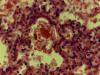

синдромов РДСН, раньше называли пневмопатиями. РДСН (син.пневмопатии,СДР) имеет несколько форм.Про какую форму Вы пишите ? РДСН (син.пневмопатии,СДР) может быть толлько у новорожденного.Этим признаётся,что ребёнок дышал,жил часы и сутки.Ничего из пневмопатий на фото не вижу. Геморрагический синдром Какое отношение геморрагический синдром при коагулопатии у матери имеет к разбираемому случаю? Не путайте с отёчно-геморрагическим синдромом. |

Да, похоже на искусственную вентиляцию.

Да, похоже на искусственную вентиляцию. еще пару фото увеличение 4х10, 20х10, 63х10, нет 40-ки Эскизы прикрепленных изображений

отечно-геморрагический син.бывает у мертворожденных? Конечно же нет.Для начала посмотрите двухтомник по детской патологии под редакцией Ивановской. честно не видела, но запросила уже все документы С этого надо было начинать.Изучите сами.Узнайте у танатолога откуда брал куски лёгких. Учитывая последние фото уверен,что это недышавшие лёгкие после проведения искусственной вентиляции . |

Добрый день! наблюдается неполное расправление просвета альвеол, альвеолярные перегородки извилистые, широкие междольковые прослойки, просвет альвеол местами выполнен свежей кровью, с примесями десквамированных альвеолоцитов, встречаются овальные, кубические альвеолоциты, местами и в просвете отдельных бронхиол имеется примеси свежих эритроцитов. Мое предварительное мнение по присланным микрофото Респираторный дистресс-синдром новорожденных. Тонут легкие и при кровоизлиянии в респираторные отделы легких. вряд ли РДС, больше похоже на общеасфиксические признаки: при исследовании других органов: острое венозно-капиллярное полнокровие (полнокровие сосудов головного мозга, мягкой мозговой оболочки, легких, миокарда, печени, почек, тимуса, селезенки, с межуточными и паренхиматозными кровоизлияниями в легких, кровоизлияниями в паренхиме тимуса, в корковом и мозговом слое почки, в капсуле надпочечника,кровоизлияния с геморрагическим пропитыванием мягких тканей гортани, интерстициальный и периваскулярный отек внутренних органов, в том числе и головного мозга; нарушения реологических свойств крови в виде эритростазов, эритросладжей в сосудах микроциркуляторного русла. Цитата Учитывая последние фото уверен,что это недышавшие лёгкие после проведения искусственной вентиляции . получается ребенок не дышал, но живорожденный??? |

получается ребенок не дышал, но живорожденный??? С чего это Вы взяли ? Читайте внимательно. С точки зрения танатолога и гистолога в одном лице,Ваш случай не представляет сложности в диагностике. Причина смерти - внутриутробная асфиксия.Изменения в лёгких - результат реанимационных мероприятий (искусственная вентиляция лёгких). Надо изучать медицинскую документацию и быть в контакте с танатологом. Прежде чем открыть тему, следовало бы располагать полной информацией. РДС Забудьте. |

еще пару фото увеличение 4х10, 20х10, 63х10, нет 40-ки Ув.коллеги! Естественно симптомы, синдромы м.б. при различных болезнях. И нельзя ограничиваться мнением ссылаясь на литературу. Есть практические наблюдения и опыт. Выносить выводы должен сам ТС. Зрительно увидел и сразу вписывать на тот или иной диагноз нельзя. Диагноз должен выставляться по этиопатогенетическим принципам с учетом патофизиологи. Я не видел и в первом и во втором микрофото массивной аспирации альвеол ЭОВ( роговых чешуек) и разорванных альвеолярных перегородок, видел только в просвете бронхов умеренное количество роговых чешуек с примесями десквамированных эпителии и отечную гомогенную жидкость. Не забывайте и еще раз напоминаю, что внутриутробно до уровня бифуркации в просвете трахей всегда бывает околоплодные воды, при рождении ребенка у новорожденных опытные акушеры и неонатологи мгновенно после первого крика отсасывает эту жидкость, тогда видно у некоторых пол кубика, у некоторых два кубика жидкости и т.д. У мертворожденных отечно-геморрагический синдром не бывает, а бывает частенько ателектазы и массивные аспирации ЭОВ именно в просвете альвеол.Что касается живорожденных - сделал ребенок самостоятельно вдох( не важно слабый без крика или сильный с криком) в считанные минуты после родов. Асфиксии бывают анте- и интранатальная, ТС нужно искать причину фонового состояния со стороны матери и плаценты, именно что привело к развитию (не важно анте- или интранатальную) асфиксии. Пусть ТС изучает все мед.документы с ЖК и Роддома. Никто не знает как эффектно проводилось ИВЛ. При ИВЛ частенько загоняют роговые чешуйки по просветами альвеол при массивной аспирации Элементов ОВ сколько бы не отсасывали. |